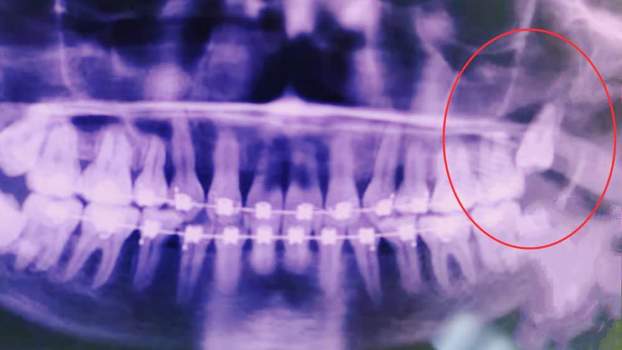

Снимок до удаления зуба

Одонтогенные гаймориты случаются довольно часто. В подавляющем большинстве случаев причинами их возникновения бывают 4,5,6-ые зубы верхней челюсти, так как их корни зачастую выстилают дно наших пазух. Но в данном, довольно редком случае, причиной стал восьмой зуб, корень которого рос под углом к в/ч пазухе (это стало известно из ортопонтограммы, предоставленной пациентом). Удаление зуба привело к деформации нижней стенки в/ч пазухи и ее сообщению с микрофлорой рта, в результате чего возник гнойный очаг.